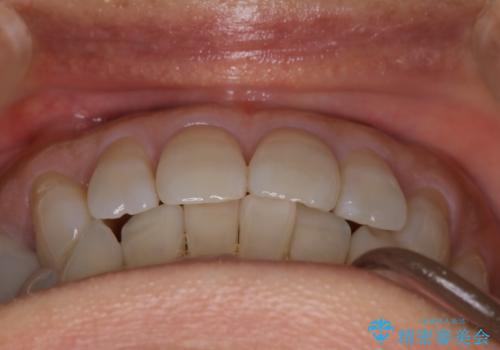

【インビザライン】下前歯だけを治したい

- 下前歯のがたつきにより唇を巻き込んでかんでしまい痛いため矯正をしたいという主訴で来院されました。今回は下顎前歯のみという強い希望があり、下顎のみのインビザライン矯正をしました。

叢生を改善するためのスペースはIPRと拡大を行いました。治療後は唇を巻き込んでしまう主訴が改善し、ご満足していただけました。